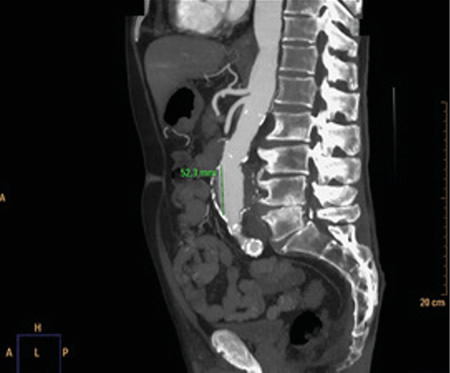

No es solo dolor lumbar: manifestación atípica del aneurisma de aorta

La rotura de aneurisma de aorta supone el síntoma principal en hasta un 25 % de los casos de la patología de aneurisma de aorta, que constituye una entidad potencialmente mortal. También puede aparecer con menor prevalencia como lumbalgia, coxalgia e, incluso, gonalgia, no comentándolo como dolor vertebral o neuropático, sino como irritación a nivel de psoas ilíaco como primera sintomatología.

Se estima que solo en un 50 % de los casos aparece la triada clásica del aneurisma, por lo que es necesario tener un alto nivel de alerta para sospecharlo, ya que la hipovolemia puede estar contenida por un hematoma peritoneal.

Figura 1

Figura 2